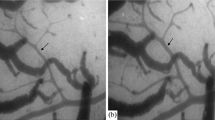

Spontaneous, rhythmical contractions, or vasomotion, can be recorded from cerebral vessels under both normal physiological and pathophysiological conditions. We investigated the cellular mechanisms underlying vasomotion in the cerebral basilar artery (BA) of Wistar rats. Pressure myograph video microscopy was used to study the changes in cerebral artery vessel diameter. The main results of this study were as follows: (1) The diameters of BA and middle cerebral artery (MCA) were 314.5±15.7 μm (n=15) and 233.3±10.1 μm (n=12) at 10 mmHg working pressure (P<0.05), respectively. Pressure-induced vasomotion occurred in BA (22/28, 78.6%), but not in MCA (4/31, 12.9%) from 0 to 70 mmHg working pressure. As is typical for vasomotion, the contractile phase of the response was more rapid than the relaxation phase; (2) The frequency of vasomotion response and the diameter were gradually increased in BA from 0 to 70 mmHg working pressure. The amplitude of the rhythmic contractions was relatively constant once stable conditions were achieved. The frequency of contractions was variable and the highest value was 16.7±4.7 (n=13) per 10 min at 60 mmHg working pressure; (3) The pressure-induced vasomotion of the isolated BA was attenuated by nifedipine, NFA, 18β-GA, TEA or in Ca2+-free medium. Nifedipine, NFA, 18β-GA or Ca2+-free medium not only dampened vasomotion, but also kept BA in relaxation state. In contrasts, TEA kept BA in contraction state. These results suggest that the pressure-induced vasomotion of the isolated BA results from an interaction between Ca2+-activated Cl− channels (CaCCs) currents and KCa currents. We hypothesize that vasomotion of BA depends on the depolarizing of the vascular smooth muscle cells (VSMCs) to activate CaCCs. Depolarization in turn activates voltage-dependent Ca2+ channels, synchronizing contractions of adjacent cells through influx of extracellular calcium and the flow of calcium through gap junctions. Subsequent calcium-induced calcium release from ryanodine-sensitive stores activates KCa channels and hyperpolarizes VSMCs, which provides a negative feedback loop for regenerating the contractile cycle.